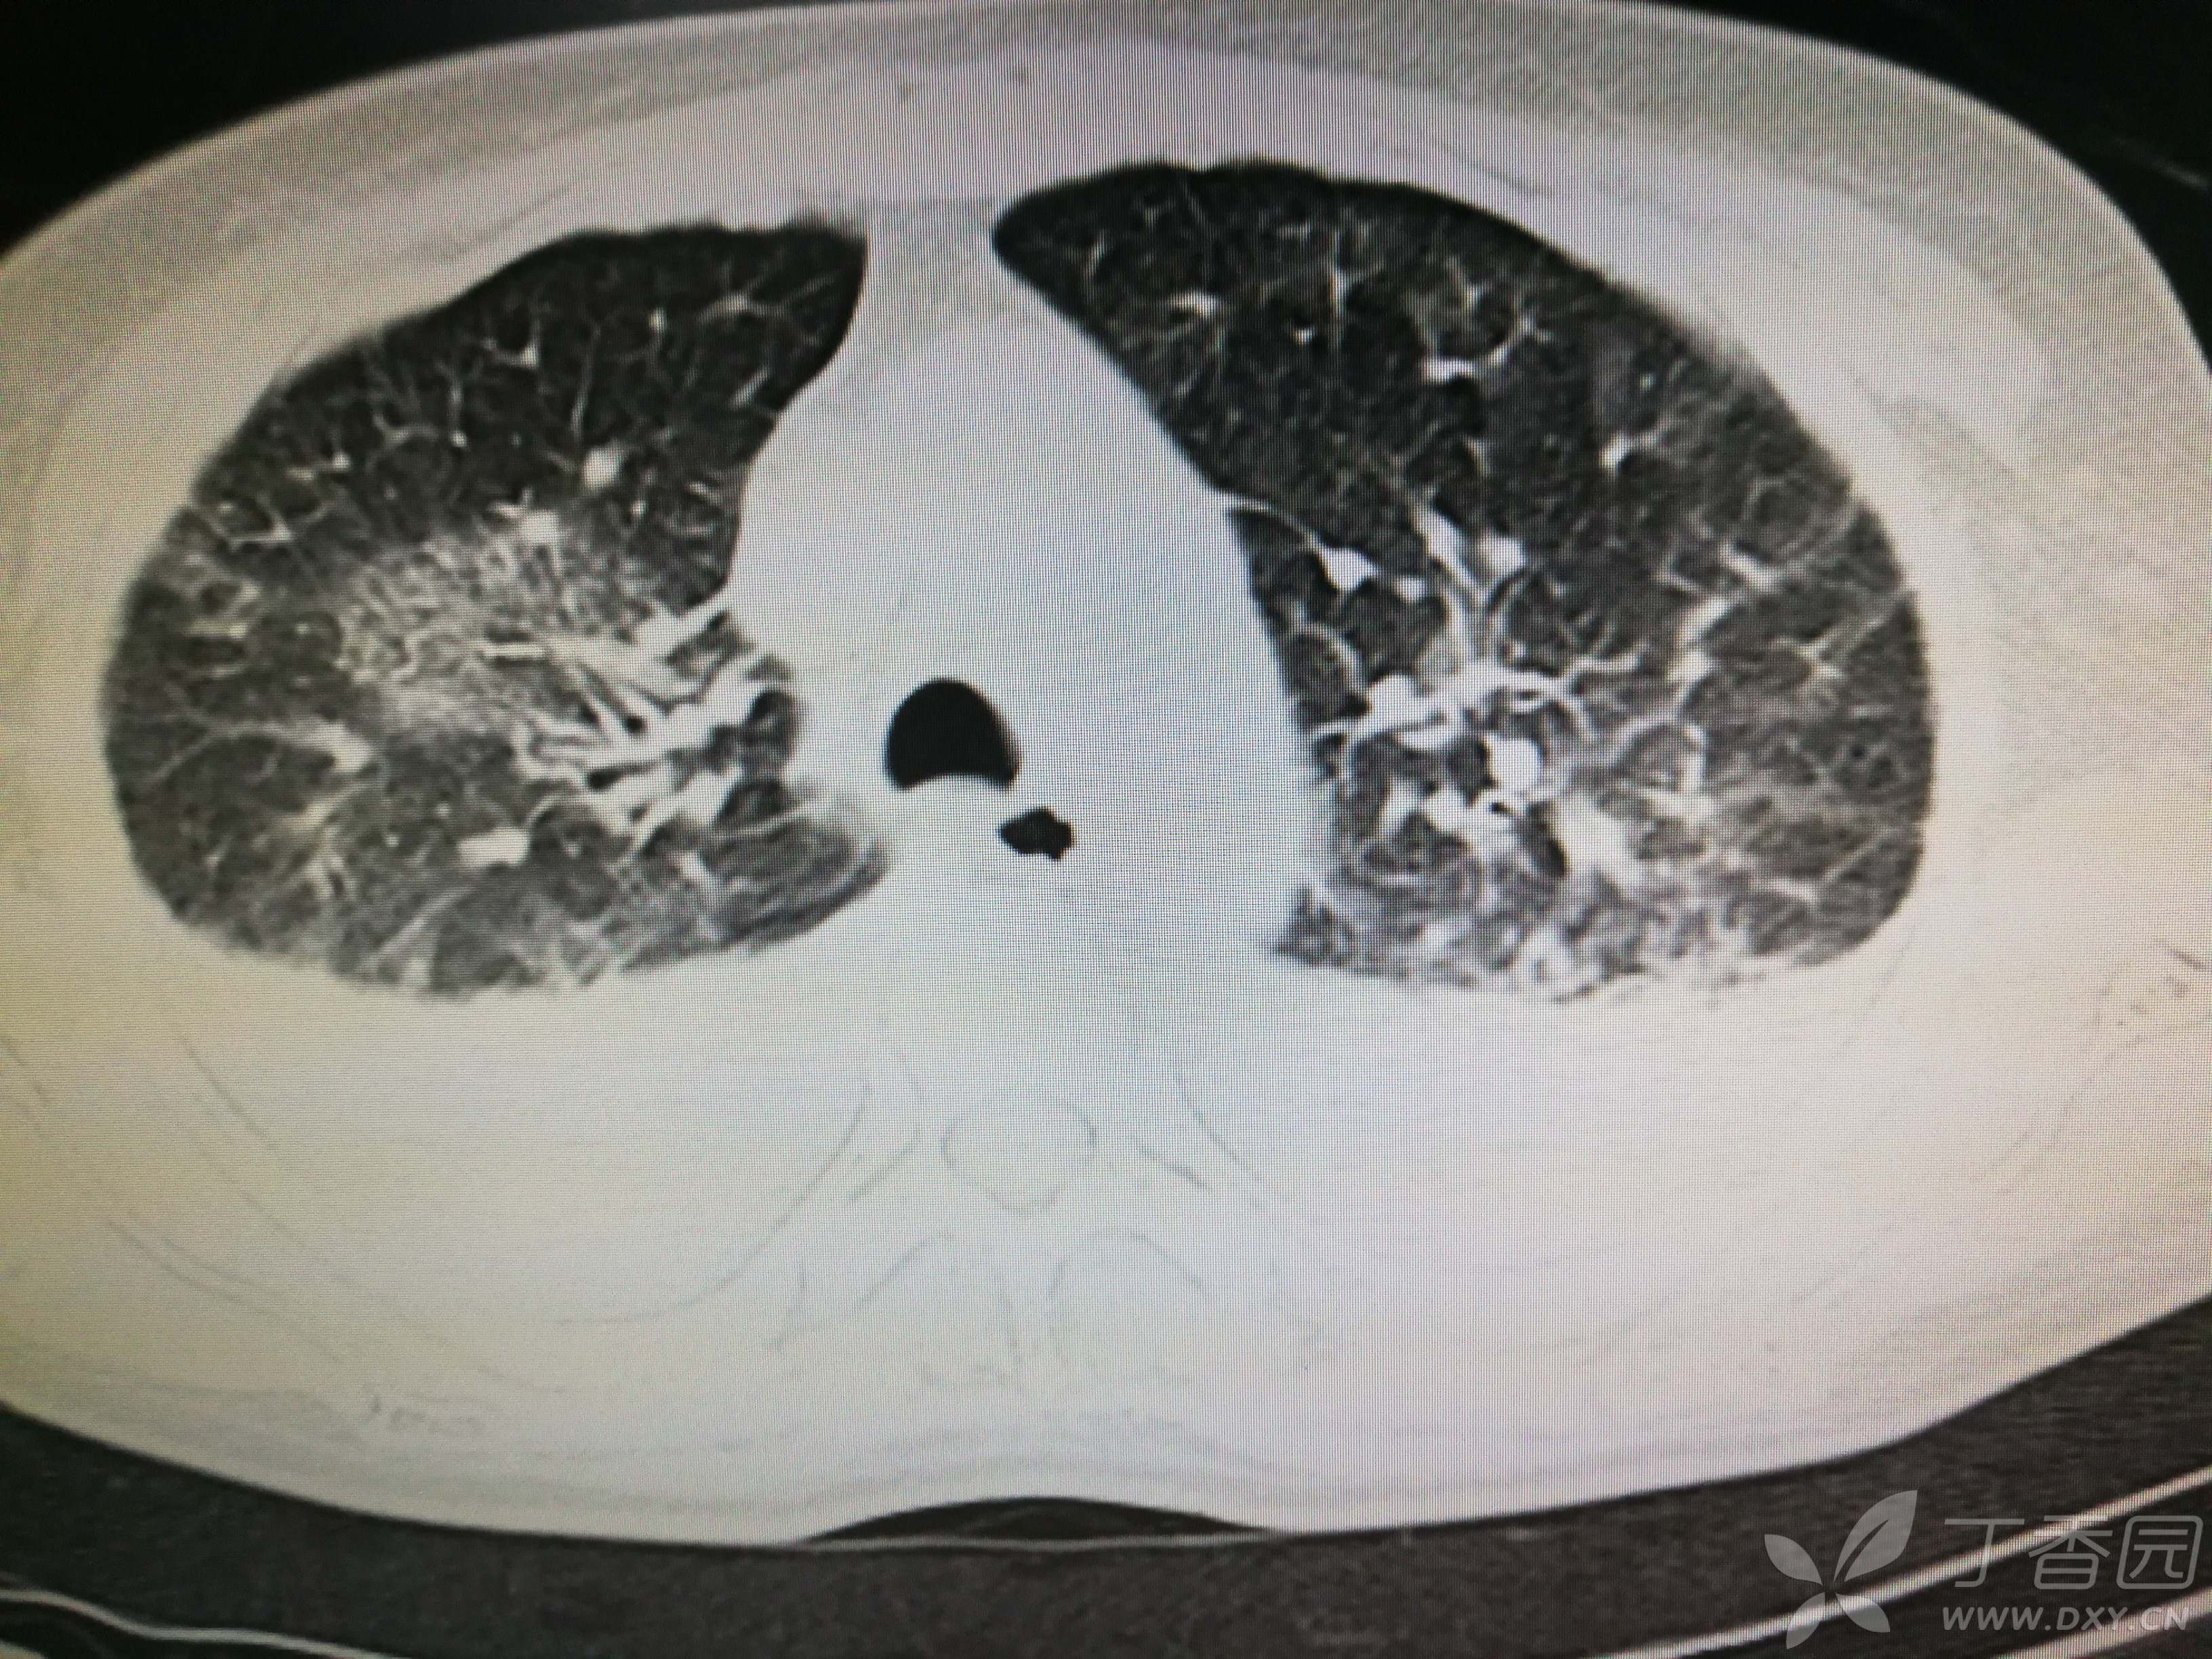

给予低分子肝素钙针抗凝、七叶皂苷钠针消肿及骨牵引固定等等治疗。入院后第四天行“左侧股骨下段骨折切开复位内固定术”(术前查双下肢彩超:双下肢深静脉血流通畅),手术顺利,术后予预防感染、预防血栓形成等治疗。术后患者无明显发热,生命体征平稳。术后第四天复查血常规:白细胞13.4×109/L,血红蛋白84g/L,血小板在正常范围。生化:白蛋白35.7g/L,余无明显异常。当天,患者开始出现轻度胸闷气急,可耐受。术后第五天患者胸闷气急加重,无胸痛,无背痛,无咯血,无意识障碍,无头晕头痛,无恶心呕吐等,急查凝血功能:纤维蛋白原降解产物12mg/L,D二聚体4000ug/L,余无明显异常。查动脉血气分析:pH7.52,氧分压62mmHg,二氧化碳分压30mmHg,碱剩余1.8mmol/L,乳酸1.0mm/L,血红蛋白86g/L。查胸部CT见下(先视频后图片):